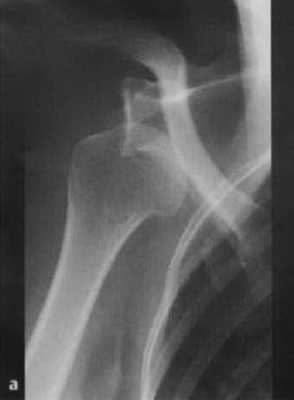

Что покажут рентгеновские снимки при вывихе плеча

- Рентгенологическое исследование в двух проекциях: прямая тангенциальная (касательная) проекция суставной полости и чрезлопаточная проекция.

Передний вывих: головка плечевой кости расположена кпереди и книзу, обычно ниже клювовидного отростка; в редких случаях она может находиться на нижней границе суставной полости.

Задний вывих: головка плечевой кости перекрывает границу суставной полости; суставная щель не визуализируется.

a,b Передний вывих плечевого сустава у женщины 46 лет после падения на вытянутую руку. (а) Рентгенологическое исследование праовго плечевого сустава в прямой проекции с ротацией противоположной стороны туловища на 40° кпереди и на (b) Y-проекция. Суставная впадина пуста. Передненижнее смещение головки плечевой кости ниже клювовидного отростка.